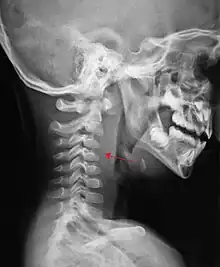

A lateral cervical spine x-ray demonstrating prevertebral soft tissue swelling (marked by the arrow) as seen in a person with a retropharyngeal abscess

X-ray of the neck often (80% of the time) shows swelling of the retropharyngeal space in affected individuals. If the retropharyngeal space is more than half of the size of the C2 vertebra, it may indicate retropharyngeal abscess.[5]